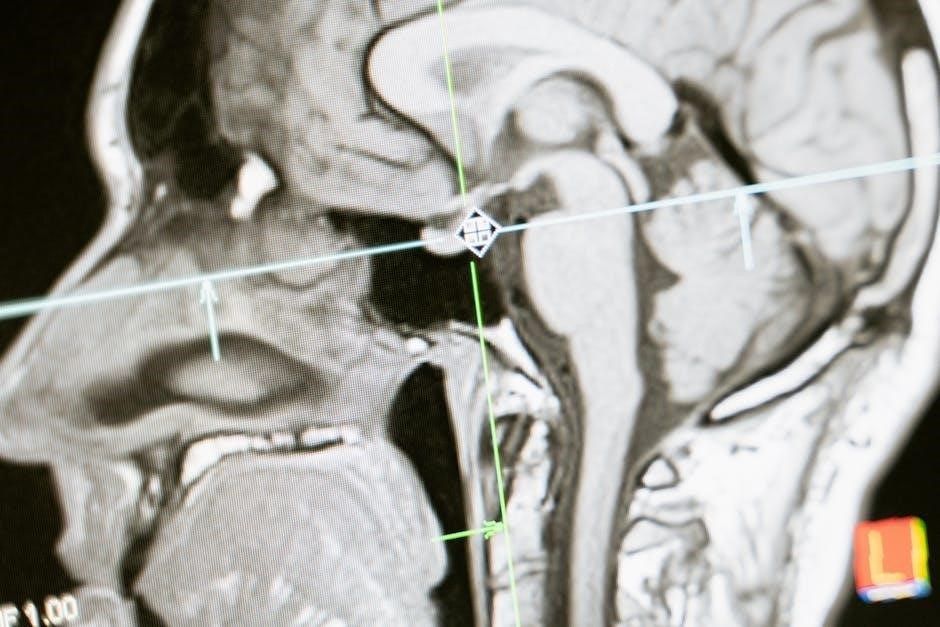

High-quality illustrations are paramount in any effective anatomy and physiology coloring workbook‚ especially when accessed as a PDF. The images should accurately represent anatomical structures‚ avoiding simplification to the point of inaccuracy. Look for workbooks that depict tissues‚ organs‚ and systems with realistic detail‚ showcasing their complex arrangements and relationships.

Illustrations should be free from ambiguity‚ clearly differentiating between various components. The level of detail should be appropriate for the intended audience – introductory workbooks may offer simpler depictions‚ while advanced resources will present more intricate anatomical features. When evaluating a PDF version‚ ensure the image resolution is sufficient to allow for clear coloring and identification of structures; blurry or pixelated images diminish the learning experience.

Furthermore‚ consider illustrations that demonstrate different views and sections of the anatomy‚ providing a comprehensive understanding of spatial relationships. Accurate depictions are crucial for building a solid foundation in anatomical knowledge;

Digital anatomy tools‚ like Human Anatomy Atlas and Complete Anatomy‚ offer 3D models complementing PDF workbooks‚ providing interactive exploration of structures.